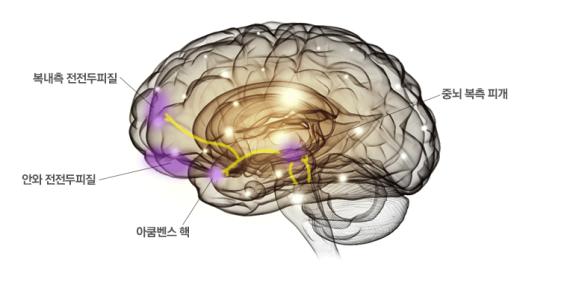

3. 중뇌에서 시작하여 피질, 변연계로 가는 도파민 회로이다.

중뇌의 복측 피개영역에서 시작하여 아쿰벤스 핵과 복내측 전전두피질, 안와 전전두피질로 가는 신경회로이며, 동기, 보상, 실행 기능을 가진 것으로 알려져 있다.

이 회로에 속하는 신경의 말단에서는 도파민이라는 신경전달물질이 분비되며, ADHD에서는 이 회로의 기능이 저하되는 것으로 알려져 있다.

반대로 ADHD 치료제는 대개 도파민의 기능을 강화하는 역할을 한다.